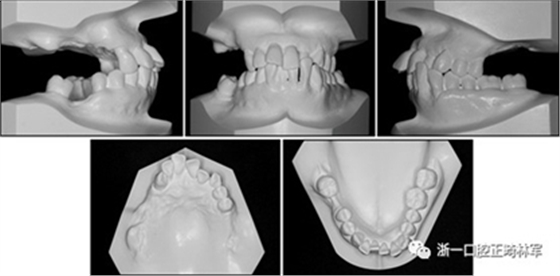

圖1. 治療前面部和口內照片

口腔內由于牙周炎,她的上頜右側第一和第二前磨牙,上頜右側第一和第二磨牙,上頜左側第一和第二磨牙以及下頜右側第一磨牙缺失。牙周探查顯示在磨牙區(qū)域和下頜骨左側側切牙區(qū)有深的牙周袋,還存在出血(表I)。上頜骨和下頜骨前牙擁擠,左側側切牙存在反合,下頜左側側切牙發(fā)過度萌出。覆蓋是5毫米,上頜切牙是唇傾的。在上頜弓中,尖牙和前磨牙是近中傾斜,右側尖牙過度萌出。而且,下頜右側第二磨牙向近中傾斜。尖牙處于I類關系,但無法評估磨牙關系(圖1和2)。

圖2. 治療前牙齒石膏模型